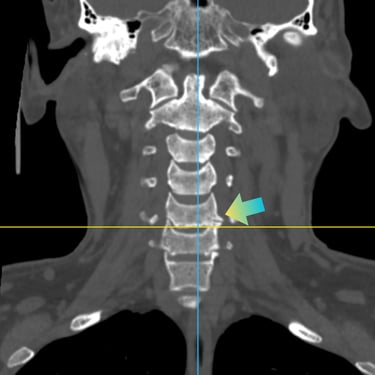

Hernia Cervical con Mielopatía: ACDF con Cage y Placa asistida con Monitoreo Neurofisiológico

La hernia cervical con mielopatía se produce por la compresión de la médula espinal, ocasionando dolor cervical, debilidad, alteraciones sensitivas y trastornos de la marcha. En casos de compromiso neurológico progresivo, la discectomía cervical anterior y fusión (ACDF) con cage y placa es una alternativa quirúrgica eficaz. La cirugía asistida con monitoreo neurofisiológico intraoperatorio permite evaluar en tiempo real la función neurológica, aumentando la seguridad del procedimiento. Este abordaje facilita una descompresión adecuada, estabilización del segmento cervical y favorece una recuperación neurológica segura y progresiva.